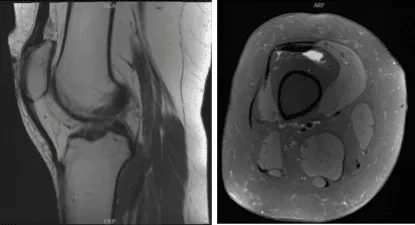

MRI of right knee

Patient returned and presented her MRI- found Tri compartment degenerative chest, with cartilage loss most pronounced in the patellofemoral compartment.

Complex tear involving the anterior horn lateral meniscus with a horizontal component extending into the body lateral meniscus with small joint effusion.